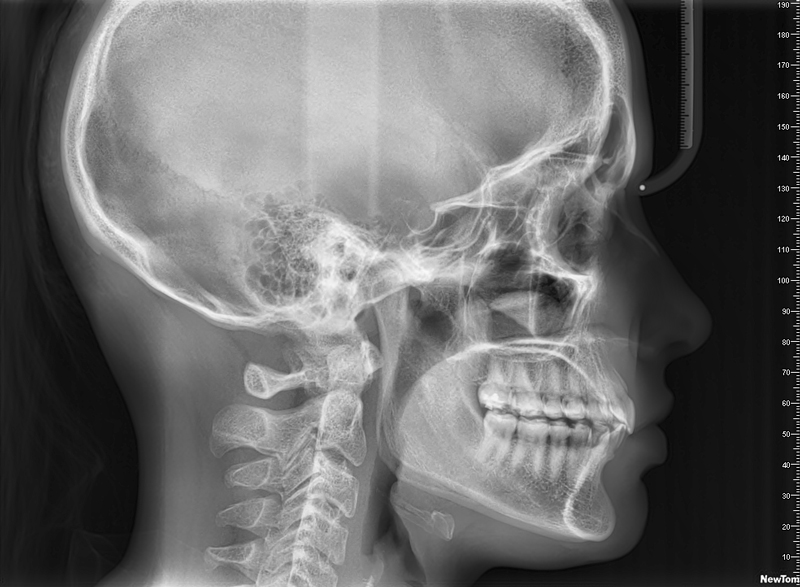

Lateral de Cráneo

• Es un estudio clave para la ortodoncia ya que permite medir los ángulos y proporciones de la estructura ósea de la cara del paciente. A su vez visualiza el progreso de la ortodoncia. Es recomendable que se acompañe de un estudio cefalométrico.